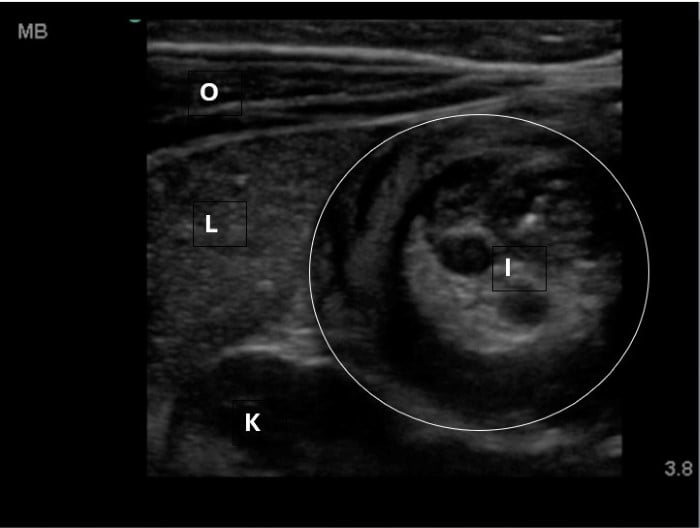

The linear probe is placed in the RLQ in the transverse position with indicator to the patient’s right. Identify the psoas muscle and iliac vessels lying medial. Once these structures are visualized, slide lateral and look superficially to identify the cecum. (Figures 1a,1b 1) Use graded compression-progressive increase and decrease of pressure to move any gas out of view. Keeping the lateral edge of the abdominal cavity in view (Figure 2), the ultrasound probe should slide cranial in traverse plane, visualizing the ascending colon until the hepatic flexure.  In this location, the colon turns just medial to the liver with the kidney deep in the view. (Figure 3) This is the most common location to identify ileocolic intussusception. If no tissue mass is identified, the probe should be turned to the sagittal plane with indicator toward the head (to keep the colon visualized in the transverse view) and moved across the transverse colon continuing to use graded compression to look for a tissue mass consistent with intussusception. Once at the splenic flexure (Figure 4), the probe should be transitioned back to the transverse orientation to interrogate the descending colon.

10-2024 Article7-3.jpgFigure 3. Hepatic flexure view in a patient with intussusception. Oblique abdominal muscles, liver, kidney visible. Intussusception will be medial to the liver and superficial to the kidney.